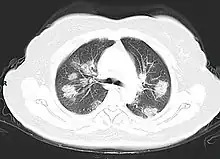

Comme pour la plupart des survivants du syndrome de détresse respiratoire aiguë, la dyspnée est le symptôme persistant le plus courant après un COVID-19 grave, avec une prévalence de 42 à 66 % après plus de 60 jours de suivi. Par exemple, parmi 1800 patients espagnols qui ont dû subir une trachéotomie au cours d'un épisode aigu, seuls 52 % ont réussi à être sevrés de la ventilation mécanique un mois plus tard. Cela s'explique par une baisse de la capacité de diffusion pulmonaire (la quantité de gaz absorbé par le sang des capillaires pulmonaires à partir du gaz alvéolaire), phénomène déjà observé chez des survivants de la grippe H1N1. L'invasion des cellules alvéolaires par le SRAS-CoV-2, ou l'inflammation périvasculaire, participent à la rupture des barrières endothéliales et épithéliales avec invasion de monocytes et de neutrophiles et extravasation d'un blastème riche en protéines[51],[52],[53],[54],[55].

Par ailleurs, environ 40 à 50 % des Covid-19 asymptomatiques pourraient présenter des anomalies radiographiques des poumons, le plus souvent des nodules en verre dépoli[56],[57]. Le verre dépoli aigu exprime un œdème, une hémorragie ou simplement une inflammation pulmonaire. Généralement il faut moins de 3 mois pour que ces nodules disparaissent[58].